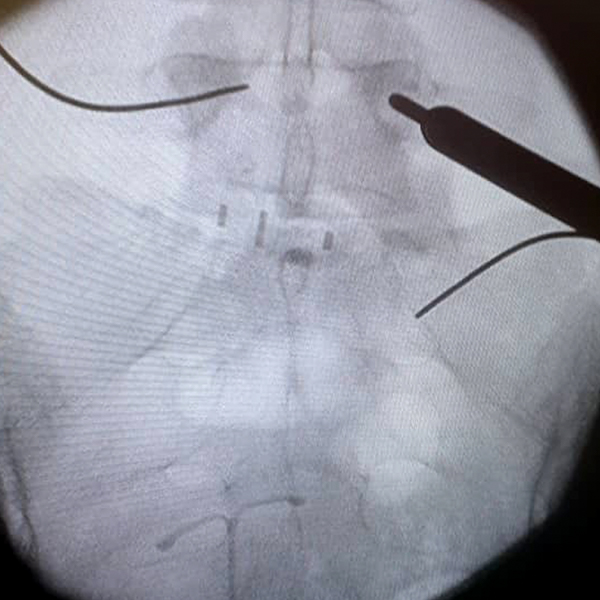

3. Colocación de los tornillos percutáneos:

Los tornillos se colocan en la parte posterior de la vértebra, de manera que el soporte entre dos vértebras está dada por la parte anterior por la caja intersomática y por la parte posterior por los tornillos. Se colocan dos tornillos por cada vértebra, uno derecho y otro izquierdo. Ellos se colocan a través de la piel por unos tubos especiales diseñados para ello a través de guías especiales que entran al pedículo. Estos tornillos se conectan finalmente por una barra longitudinal. Toda la colocación de los tornillos es viendo una cámara en vivo de Rx.